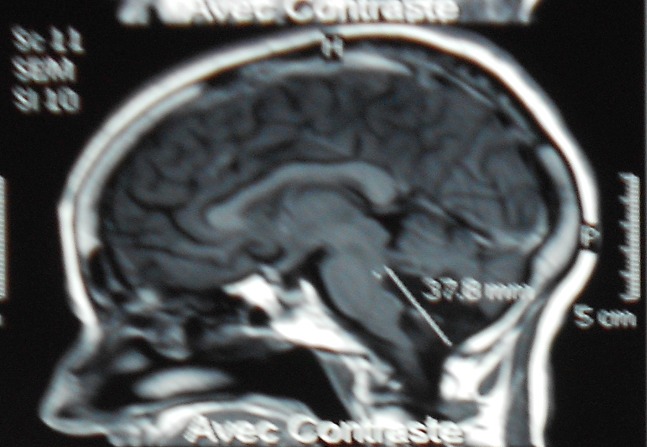

Figure 2.

IRM cérébral en coupe sagittal séquence T1 gado; montrant une lésion kystique hypointense, ne prenant pas le contraste au niveau de la grande citerne et le quatrième ventricule